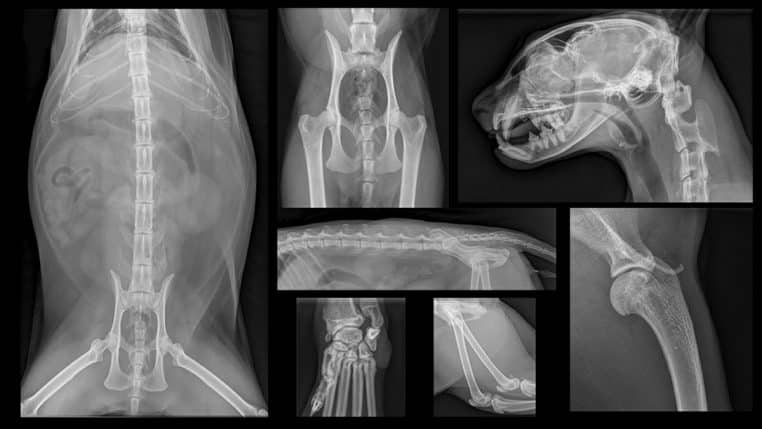

Les examens en question comprennent des radiographies, des analyses de sang et bien d’autres. Au final, Tate a dû payer plus de 760 € au profit de la clinique. Une énorme somme qu’elle débourse sans broncher, si c’est pour le bien de son animal de compagnie. Au moment de dévoiler le diagnostic, le médecin n’a pas pu s’empêcher de rire !